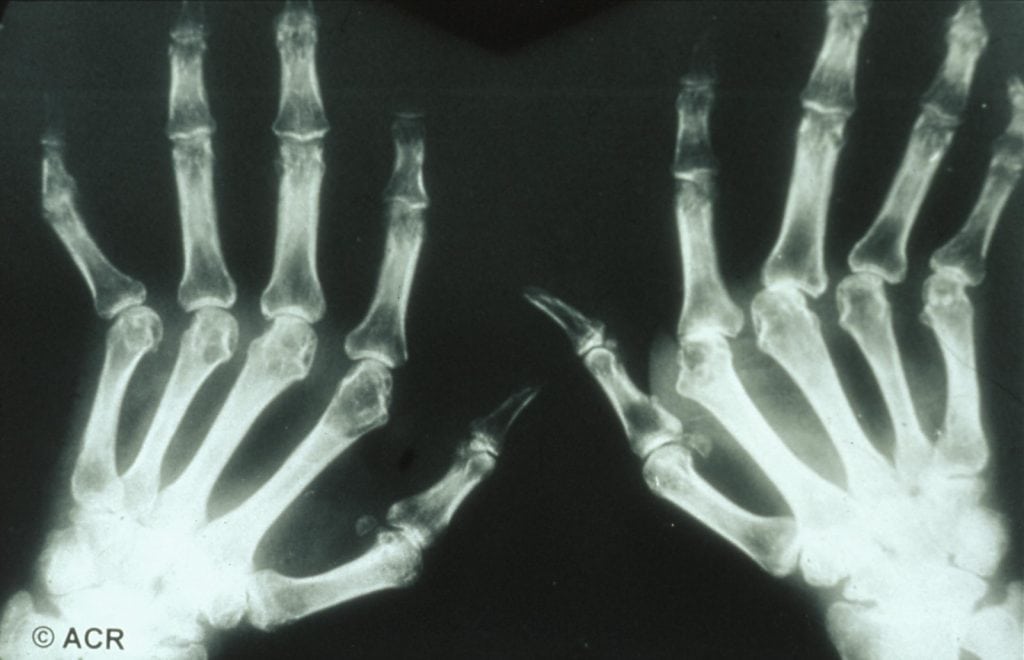

Auch die Zeit bis zur Diagnosestellung weist geschlechtsspezifische Unterschiede auf: Häufig dauert es länger, bis bei Frauen die Diagnose einer rheumatischen Erkrankung gestellt wird. Unterschiedliche Ergebnisse in der Diagnostik können zu dieser Verzögerung beitragen: bei Männern mit einer entzündlichen Wirbelsäulenerkrankung sind häufiger erhöhte Entzündungsmarker im But und knöcherne Veränderungen im Röntgenbild sichtbar. Bei Frauen sind diese Untersuchungen häufiger unauffällig, obwohl sie bereits Symptome einer entzündlich-rheumatischen Erkrankung zeigen. Eine verzögerte Diagnose geht oft mit einem langen Leidensweg der Patient:innen einher und kann zu irreversiblen Folgeschäden führen, wenn die rheumatische Erkrankung nicht frühzeitig behandelt wird.